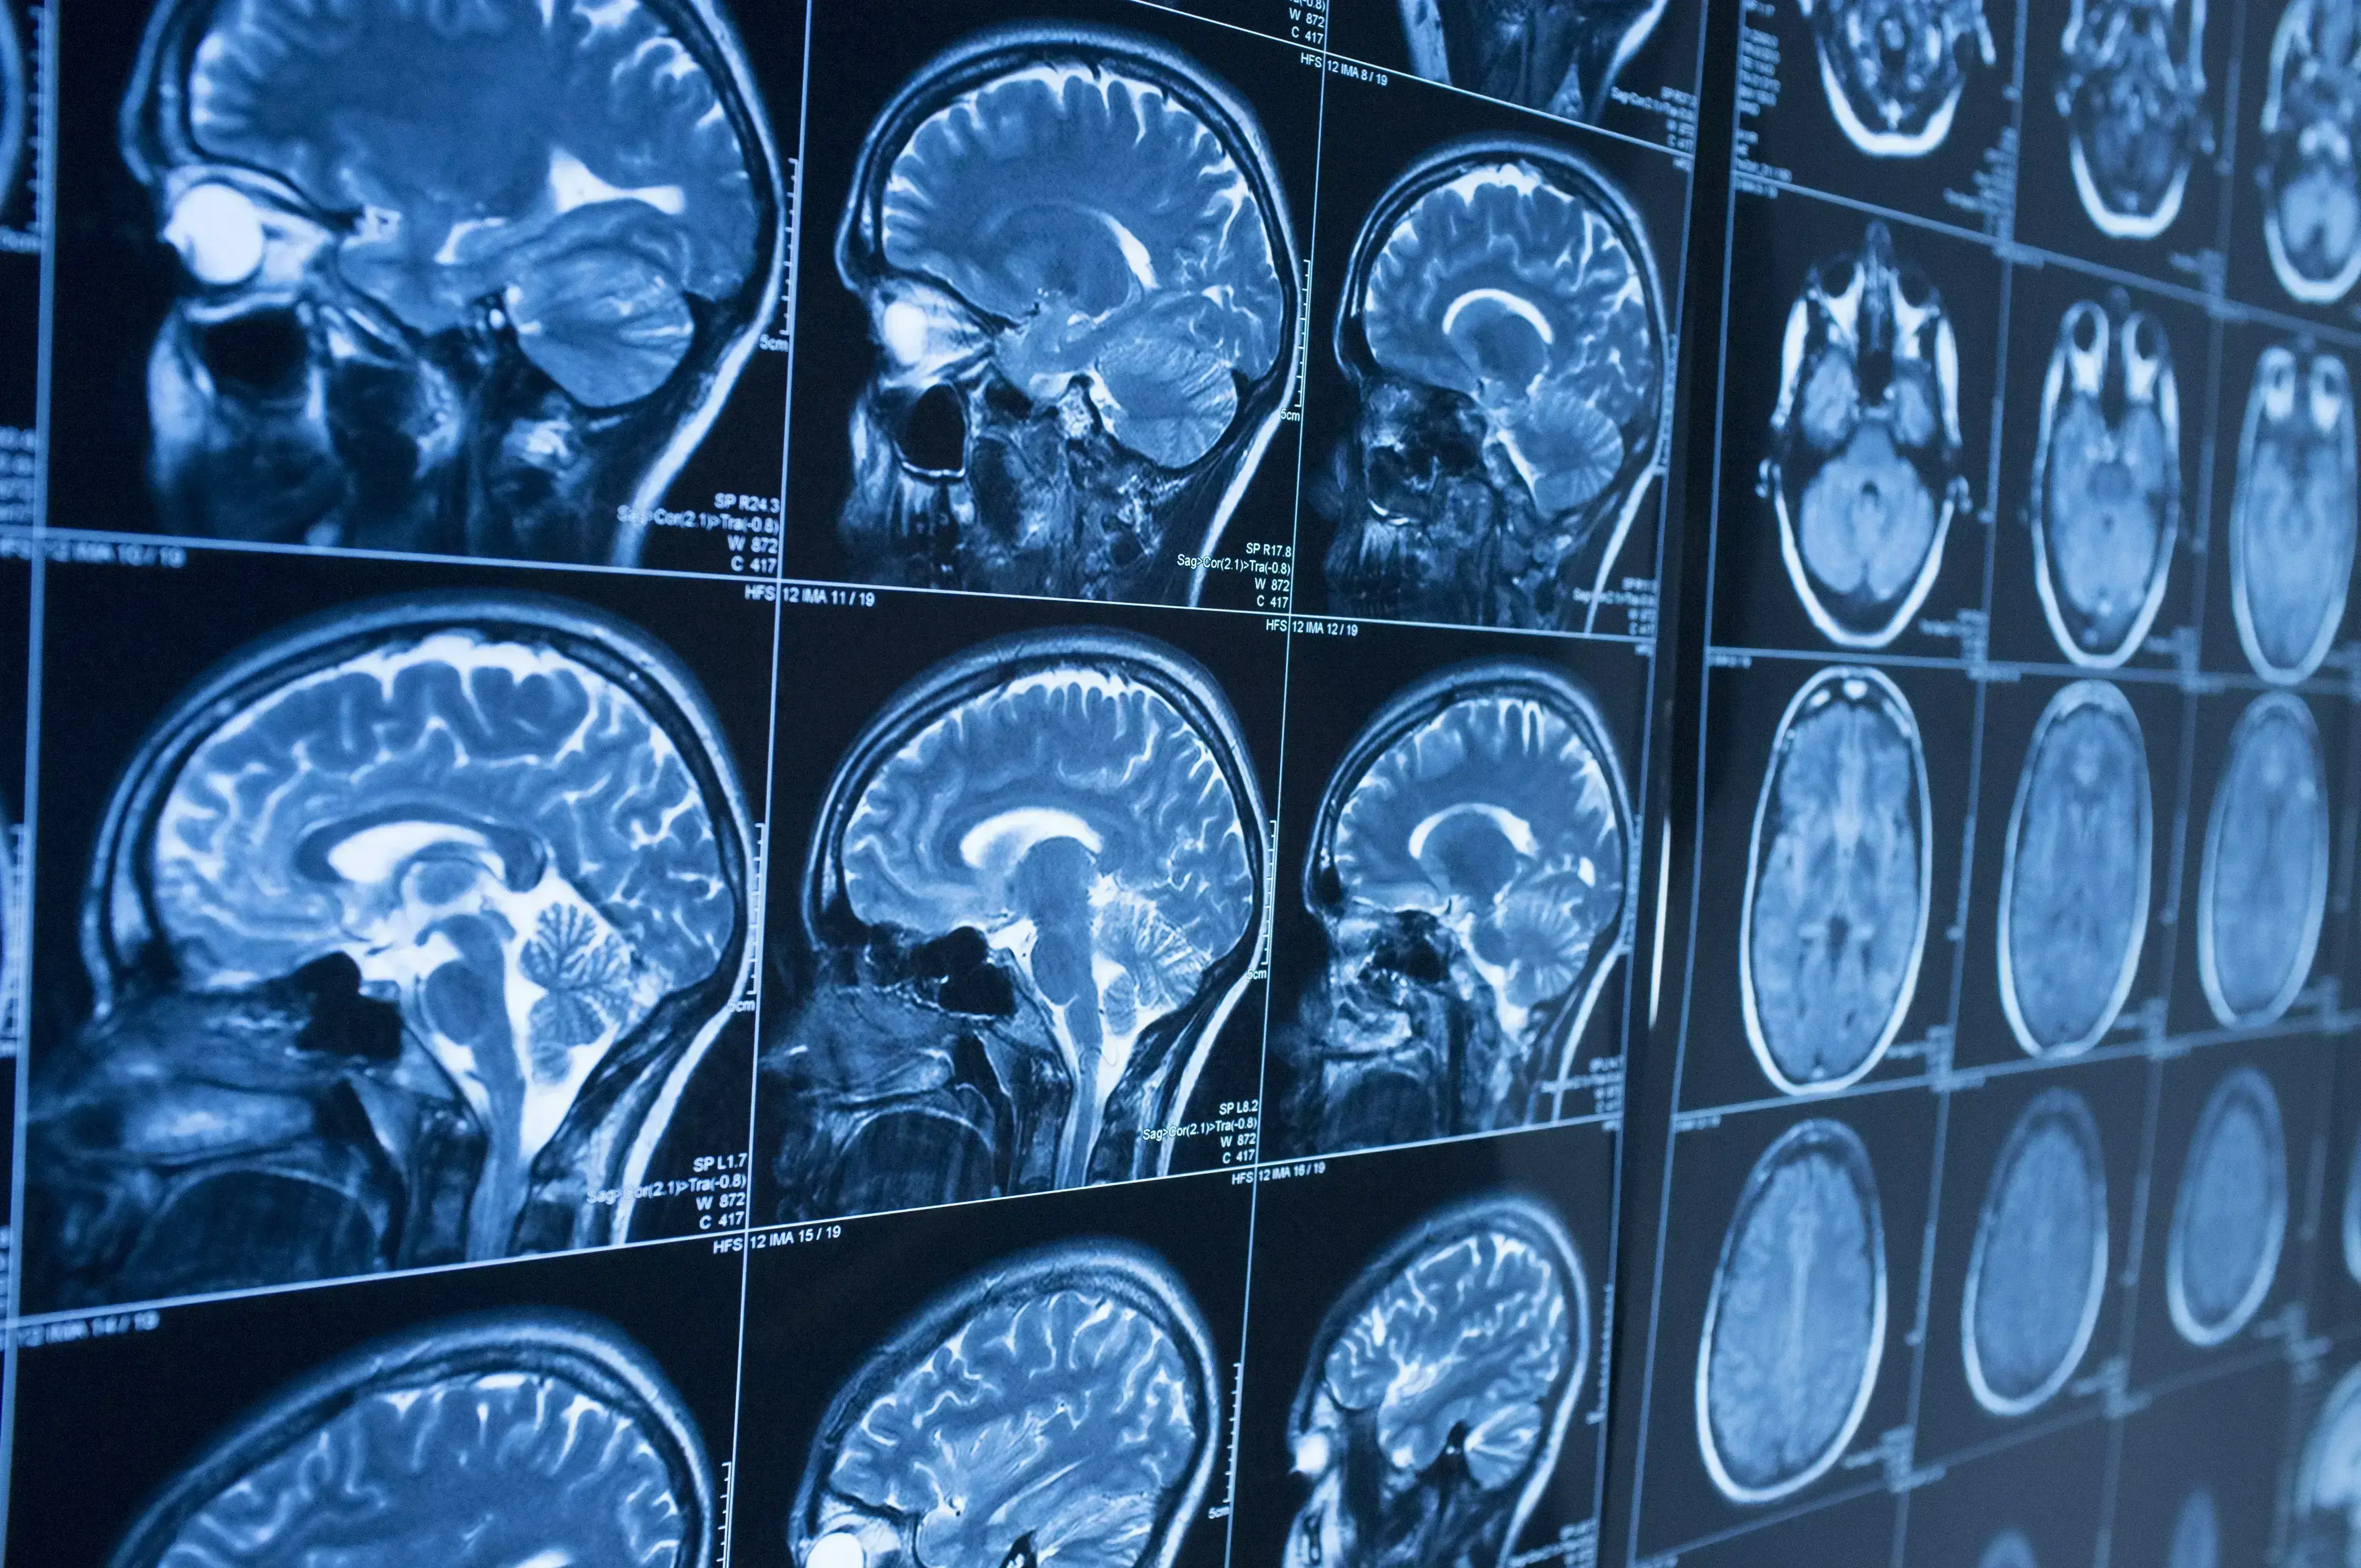

Increasing severity of Alzheimer’s disease (AD) is associated with a progressive breakdown in anatomical brain connections that can be revealed by functional MRI.1 Such use of advanced imaging to map changes in the brain connectome was among several areas of progress picked out by Massimo Filippi (San Raffaele Scientific Institute, Milan, Italy) in the EAN 2020 Virtual Congress session devoted to news in neuroimaging.

알츠하이머병 중증도 심화는 해부학적인 점진적 뇌 연결의 붕괴와 관련되어 있으며, 이는 기능적 MRI로 밝혀낼 수 있습니다.1 EAN 2020 신경 영상 분야 동향에 관한 가상 회의 세션에서 마시모 필리피 교수(Massimo Filippi, 이탈리아 밀라노 산라파엘레과학연구소)는 관련 연구 분야의 발전 사례들을 소개하며, 그 중 하나로 이와 같은 뇌 연결 상태의 변화를 발견하기 위한 진보된 이미징 기술의 이용에 관해 설명했습니다.

The Milan group has already shown that -- in people with a similar degree of cognitive impairment -- functional MRI allows early-onset AD to be distinguished from behavioral variant frontotemporal dementia.2

밀라노 연구진의 기존 연구 결과에 따르면, 인지기능 장애 정도가 유사한 환자들을 대상으로 기능적 MRI를 이용하면 조발성 알츠하이머병과 행동변종 전두측두엽 치매를 구분해낼 수 있습니다.2

In other developments, use of ultra high-field MRI has now been shown to increase the detection of amyloid plaques that are evident post mortem. The ability to image pathology at high spatial resolution may offer a new means for the in vivo assessment of amyloid load in patients with AD.

다른 개발 사례에서, 초고자장 MRI(ultra high-field MRI)의 활용은 아밀로이드 플라크 검출능을 증대시켰으며, 이는 사후부검에서 확인되었습니다. 또한, 고공간 분해능(high spatial resolution)을 이용한 병리 이미징 기술은 알츠하이머병 환자의 체내 아밀로이드 부하 평가를 위한 새로운 방법으로 활용될 수 있습니다.

Professor Filippi also drew attention to the growing role of deep learning through which artificial intelligence systems compare brain scans from normal controls and people with dementia to identify patterns that will refine diagnosis and prognosis.3

필리피 교수는 인공 지능 시스템으로 정상 집단과 치매 환자의 뇌 스캔을 비교하고 여기에서 나타나는 패턴의 차이를 파악해 진단 및 예후 측정 방법을 개선하기 위해 활용하는 딥 러닝 기술의 역할 증대에도 주목했습니다.3

In an addition to existing knowledge about the prognostic value of structural MRI, a study from the Alzheimer's Disease Neuroimaging Initiative (ADNI) shows that annual decrease in volume predicts conversion from mild cognitive impairment to AD only when baseline volume exceeds a certain threshold. This finding has implications clinically, but also for the use of atrophy rate as an endpoint in trials.4

구조적 MRI의 예후적 가치에 관한 기존 지식 외에도, 알츠하이머병 신경영상 이니셔티브(ADNI)가 실시한 한 연구에 따르면, 기저 부피가 일정 수준 이상인 경우 연간 감소하는 부피를 통해 경도 인지 장애에서 알츠하이머병으로의 진행을 예측할 수 있습니다. 이 연구 결과는 임상적으로 중요할 뿐만 아니라 임상 시험에서 위축 속도(atrophy rate)를 평가변수로 이용할 수 있다는 점에서도 의의가 있습니다.4